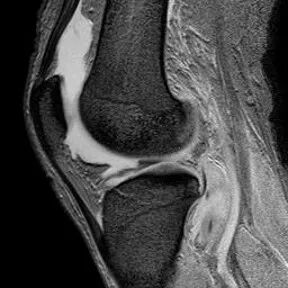

半月板撕裂定义与显示

1、半月板显示:以T2-WI加脂肪抑制为最好.2、半月板病变:最常见损伤是撕裂伤3、病因:慢性退变性撕裂和急性外伤性撕裂4、诊断方法:当半月板内出现线样高信号到达其游离缘或关节面时,即可诊断半月板撕裂5、病变信号变化:T1WI为线样稍高信号,T2(FS)或T2*WI信号更高6、半月板球形及线行高信号影未达关节面,为其慢性损伤或退行性改变(变性)7、MR诊断半月板撕裂的准确度达90-97%,特异性为94%,假阳性高于假阴性,主要是将膝横韧带与外侧半月板相邻的国肌腱鞘等误认为半月板撕裂.

半月板斜行撕裂

最常见类型:斜行撕裂表现为:在矢状面上见III级高信号到达半月板关节面的上缘或下缘